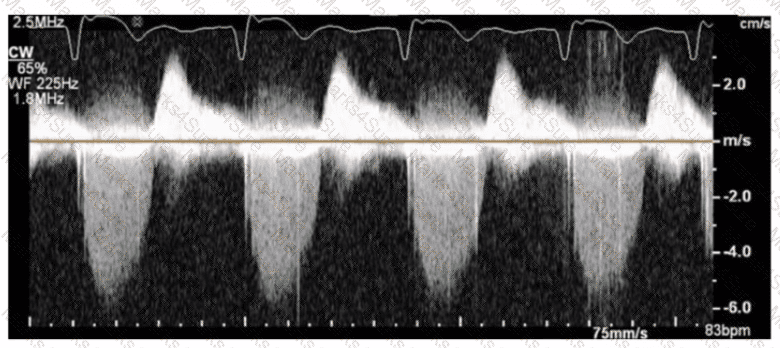

Which Doppler signal is most consistent with significant aortic valve regurgitation?

Which next step is appropriate after obtaining the Doppler signal in this image?